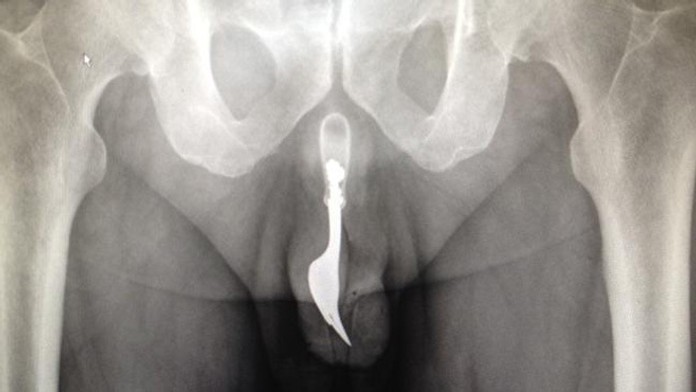

Vidlička v penise

Lekári v austrálskej Canberre vybrali 70-ročnému mužovi z penisu desaťcentimetrovú vidličku, ktorú si tam strčil v snahe dosiahnuť sexuálne uspokojenie. Muž prišiel na pohotovosť s krvácajúcim penisom, pričom lekárom povedal, že vidličku si strčil do močovej trubice približne dvanásť hodín predtým. Vidličku nebolo zvonka vidieť, dala sa však nahmatať a jej presnú polohu doktori zistili pomocou röntgenu. Následne zvažovali niekoľko možností, ako cudzí predmet z tela odstrániť. Nakoniec sa rozhodli použiť lekárske kliešte a množstvo lubrikantu, pričom muž bol počas zákroku v celkovej anestézii.